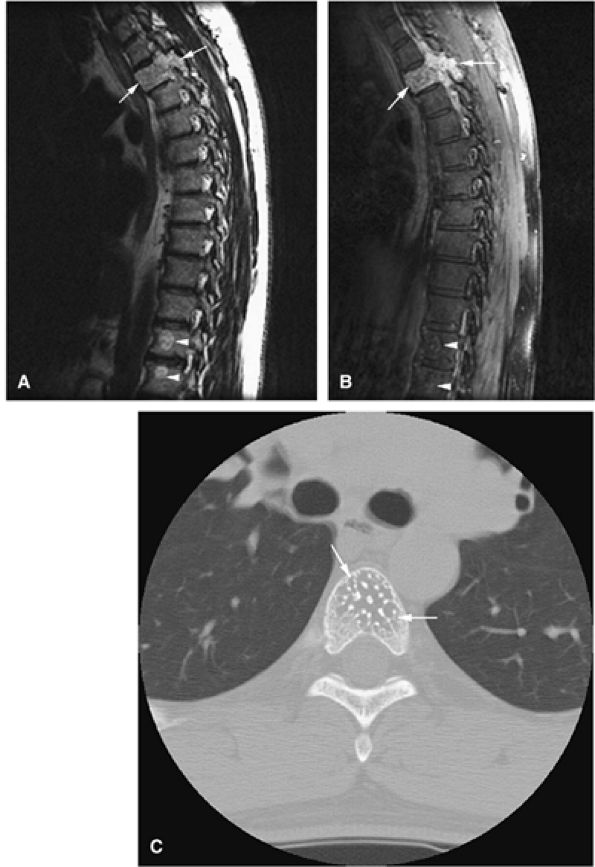

FIGURE 14-90 ● Metastatic renal cell carcinoma involving the L1 and L3 vertebral bodies is seen on sagittal (A) and axial (B) CT images. The CT scan reveals the lytic destruction (arrows) in precise detail. (C) This sagittal STIR image shows hyperintense tumor with involvement of the posterior elements and extension into the spinal canal, causing cord compression. Marrow infiltration of the L3 vertebral body (arrowhead) is noted.